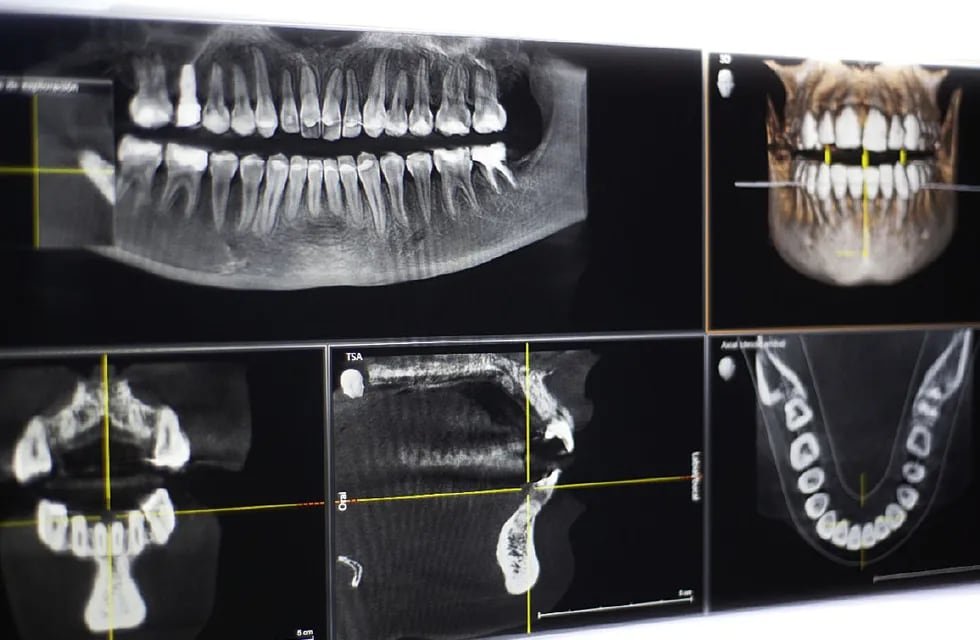

¿Qué es una radiografía panorámica dental?

Una radiografía panorámica dental es una imagen que muestra toda la boca, dientes y mandíbula en una sola imagen.

Se realiza para detectar caries, problemas en las encías, tumores, quistes, y evaluar la posición de los dientes y las estructuras óseas.

- Permite obtener una visión general de la boca y estructuras adyacentes.

- Ayuda a detectar problemas dentales y óseos que no son visibles a simple vista.

- Es una herramienta importante en el diagnóstico y planificación de tratamientos dentales.